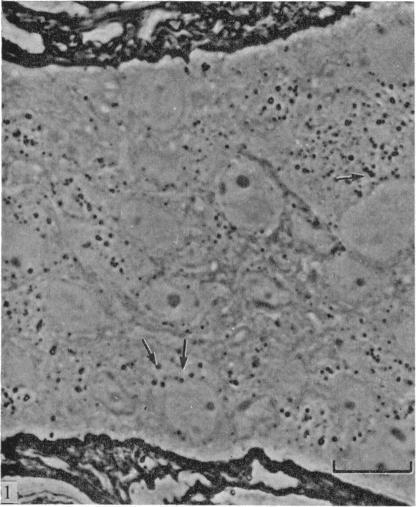

An in vitro guinea-pig preparation comprising the inferior mesenteric ganglion (IMG), the colonic nerves, and a segment of the distal colon was used to study the uptake and retrograde transport of horseradish peroxidase by intact neurons. Peroxidase rapidly penetrated the colonic wall from the lumen and was taken into autonomic nerves by pinocytotic vesicles, usually of the coated variety. The peroxidase subsequently appeared in long vesicles within the axons, and, 24 hours later, could be detected in many neuronal perikarya throughout the IMG. The similarities between the modes of uptake of peroxidase by damaged and intact axons are discussed.

采用一种包含肠系膜下神经节(IMG)、结肠神经和一段远端结肠的体外豚鼠制备物,来研究辣根过氧化物酶在完整神经元中的摄取和逆向运输。过氧化物酶迅速从肠腔穿透结肠壁,并通过通常为有被小泡类型的胞饮小泡被摄取到自主神经中。过氧化物酶随后出现在轴突内的长小泡中,并且在24小时后,可在整个IMG的许多神经元胞体中检测到。文中讨论了受损轴突和完整轴突摄取过氧化物酶方式之间的相似性。